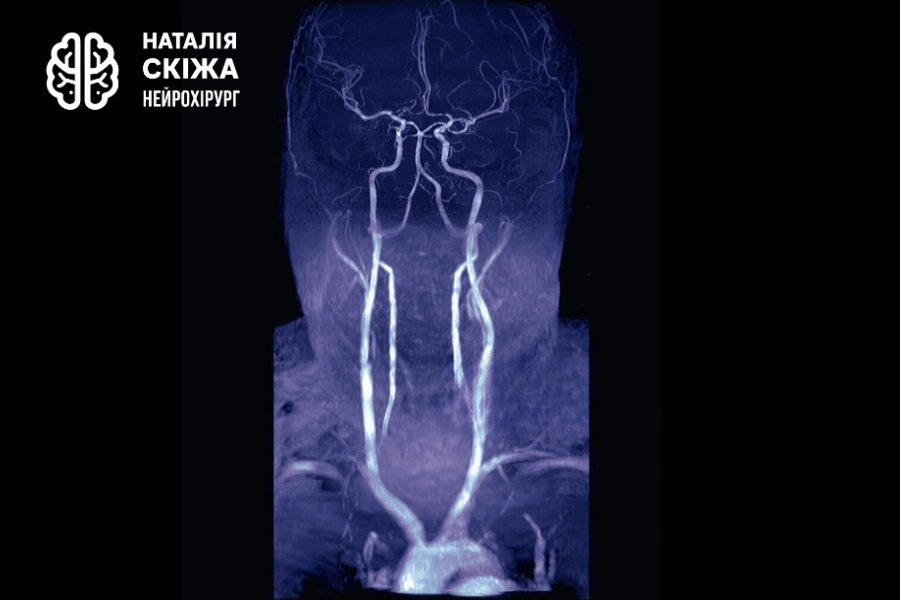

МРТ судин голови та шиї: виявлення аневризм і порушень кровообігу

Коли лікар призначає МРТ судин голови або МРТ судин шиї, (мрт шийного відділу хребта) найчастіше мається на увазі так звана МР-ангіографія (МРТ ангіографія) — спеціалізований різновид магнітно-резонансної томографії, спрямований на детальне вивчення судинного русла. Це дослідження дозволяє побачити як великі, так і дрібні артерії та вени, оцінити їхню форму, напрямок, діаметр і стан стінок. Завдяки цьому лікар може виявити звуження або розширення судин, ділянки порушеного кровотоку, а також небезпечні утворення, такі як аневризма чи судинні мальформації.

МРТ судин голови та шиї є найінформативнішим методом діагностики, який дозволяє побачити навіть мінімальні зміни у кровоносних судинах. Завдяки високій роздільній здатності МР-ангіографія дає можливість побачити судини у тривимірній проєкції, визначити ділянки звуження, розширення чи перекриття потоку крові та точно встановити характер ураження.

Аневризма — це одна з найпоширеніших і найнебезпечніших патологій, які виявляє МРТ судин. Це локальне випинання стінки артерії, яке може тривалий час залишатися безсимптомним, але водночас створює серйозну загрозу розриву. На томографічних зображеннях аневризма виглядає як мішкоподібне або веретеноподібне розширення судини, що відходить від основного русла. Її своєчасне виявлення дає змогу лікарю обрати правильну тактику лікування — від спостереження до хірургічного втручання, що нерідко рятує пацієнтові життя.

Стенози і оклюзії

Не менш важливим є виявлення стенозів і оклюзій, тобто звужень або повних перекриттів судинного просвіту. Такі зміни часто пов’язані з атеросклерозом, тромбозами чи запальними процесами судинної стінки. МР-ангіографія дає змогу оцінити ступінь звуження, побачити бляшки, порушення рівномірності кровотоку та визначити ризик ішемії головного мозку. Це особливо важливо для пацієнтів із підвищеним тиском, підозрою на інсульт або хронічні порушення пам’яті й концентрації.